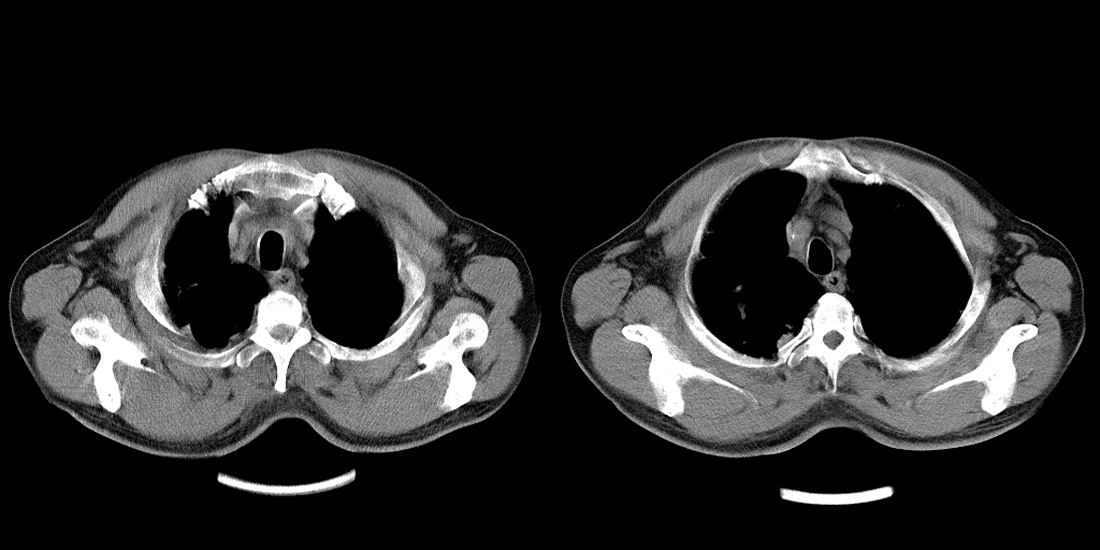

标题: CT10251:男性56岁,结核球? [打印本页]

标题: CT10251:男性56岁,结核球?

56岁男性,低热、消瘦,曾x线诊断肺结核。

两肺结核,左肺结核球。

双肺结核伴左上肺结核球形成

两肺多形性病变,支持肺结核.

两肺多形性病变,且在结核好发部位。支持肺结核.